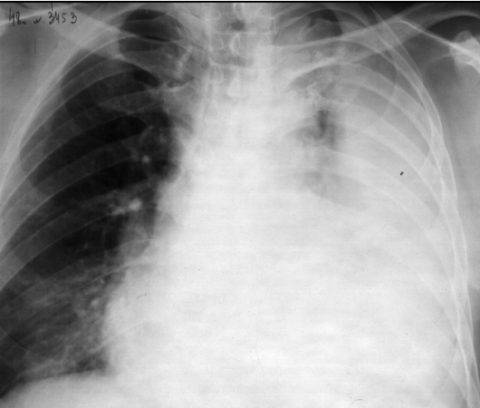

Что показывает компьютерная томография легких

На снимках рентгенолог видит картину вирусного поражения, которая в общих чертах мало отличается от картинки при гриппе. То есть поставить диагноз именно ковидной пневмонии по КТ нельзя.

Характерными признаками действия вируса будут изменения легочных полей в виде очагов (от одиночного до диффузных). Вирусная пневмония выглядит на томографии легких как совокупность типичных изменений.

- «Матовое стекло» — очаг просветления легочного поля из-за снижения воздушности в сочетании воспаления и утолщения межальвеолярных перегородок, заполнения альвеол жидкостью.

- Очаги округлые, могут сливаться между собой и распространяться на большую часть легочного поля. Чаще располагаются на периферии ближе к плевре. Чаще в нижних сегментах.

- «Булыжная мостовая» — утолщение пространства между легочными дольками, за счет чего они выглядят, как разрозненные части дороги.

- Консолидация — уплотнение легочной ткани за счет заполнения альвеол жидкостью.

- Симптом обратного ореола — кольцо консолидации вокруг участка “матового стекла”

- «Воздушная бронхограмма» — просвет бронха, пересекающего участок уплотнения легкого.

- Отмечается чаще двустороннее поражение.

- В отличие от бактериальной пневмонии реже наблюдается усиление легочного рисунка.